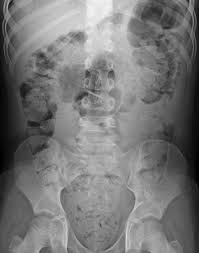

- 중년 이후에 갑자기 변비가 생기고 점점 심해지는 경우라면 대장암 가능성도 고려해야 합니다. 평소 대장 내시경을 안 하던 사람들 중에 암이 커져서 장을 막을 때가 되어서야 겨우 내시경을 해서 암이 늦게 발견되기도 하기 때문입니다. 그러므로 최근 2~3년 내에 대장내시경을 하지 않았다면 심한 변비에 내시경 검사를 고려해 봐야 합니다.